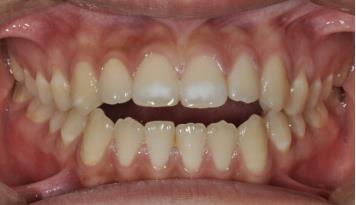

1. 前牙反合

前牙反合,俗称“地包天”,是指上下颌牙齿咬合时,下颌前牙咬在上颌前牙的外面。前牙反合随着患者的生长,症状会逐渐加重,往往造成上颌骨发育不足、下颌骨发育过度,表现为凹面型,对患者的美观、功能及心理健康均带来了极大的不良影响。乳牙列时期的前牙反合一般在3-5岁左右进行。混合牙列的前牙反合一般在8-9岁左右。

矫治方法:前牙反合的患儿往往伴有咬上唇、伸下巴、口呼吸等不良习惯。因此,应首先纠正其不良习惯。口呼吸习惯应进行耳鼻喉科会诊处理,检查其是否伴有鼻咽部疾病,排除鼻咽部疾病后,再进行纠正。对于乳牙列,常用的矫治器为合垫舌簧矫治器;对于混合牙列,常用的矫治器为前方牵引矫治器和FRⅢ矫治器。